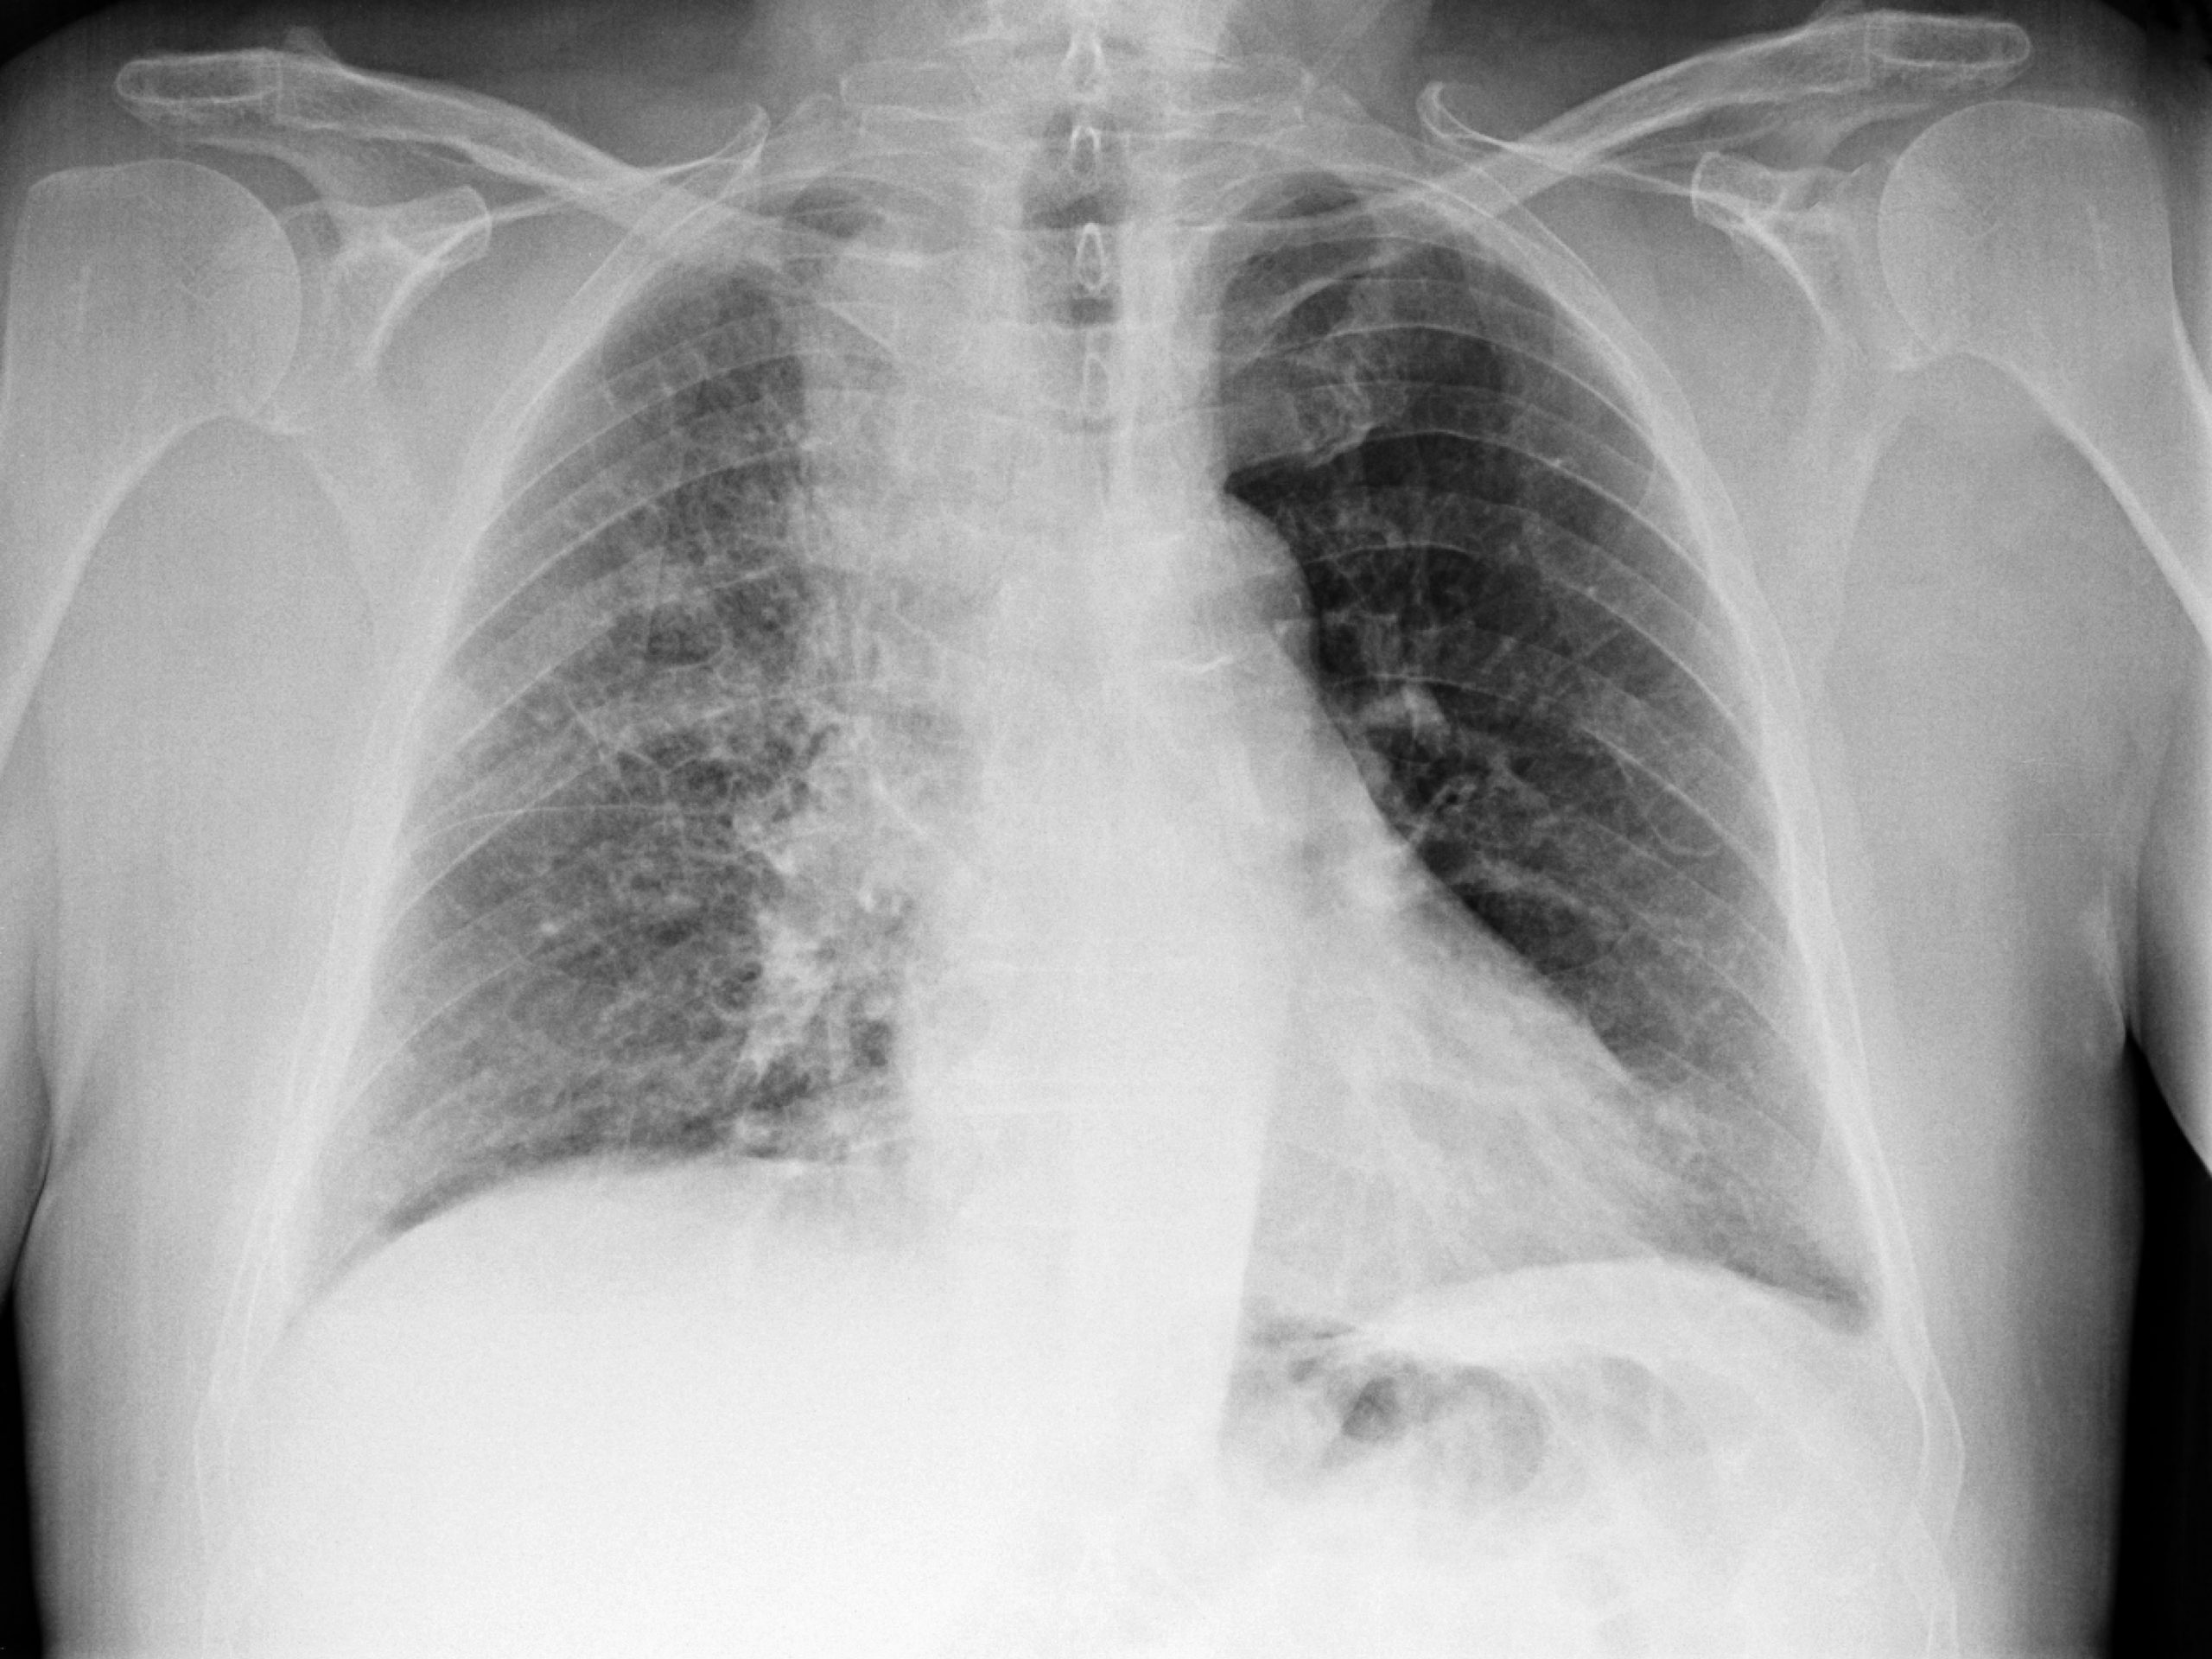

Kot opozarja onkologinja, ima polovica bolnikov z odkritim rakom pljuč že napredovalo (razsejano oziroma metastatsko) obliko bolezni. To pomeni, da se je bolezen že razširila izven pljuč, kar pomeni, da je neozdravljiva. Večino bolnikov, katerim bolezen odkrijejo v zgodnjih stadijih bolezni, ko bolezen še ni razsejana, lahko pozdravijo.

- Stadij III – gre za lokalno napredovali rak pljuč. Tumor je bodisi velik in/ali prerašča pomembne sosednje organe, s tumorskimi celicami pa so zajete tudi nekoliko bolj oddaljene bezgavke v prsnem košu. Po petih letih je živih približno 40 odstotkov bolnikov.

- Stadij IV – v tem stadiju se je rak razširil po pljučih in/ali v organe izven pljuč, kar imenujemo razsejana ali metastatska bolezen. Preživetje je odvisno ali gre za drobnocelični ali nedrobnocelični rak pljuč. Pri nedrobnoceličnem je povprečno preživetje dve leti (tudi več z novimi tarčnimi zdravili ali imunoterapijo), pri drobnoceličnem pa manj kot eno leto.